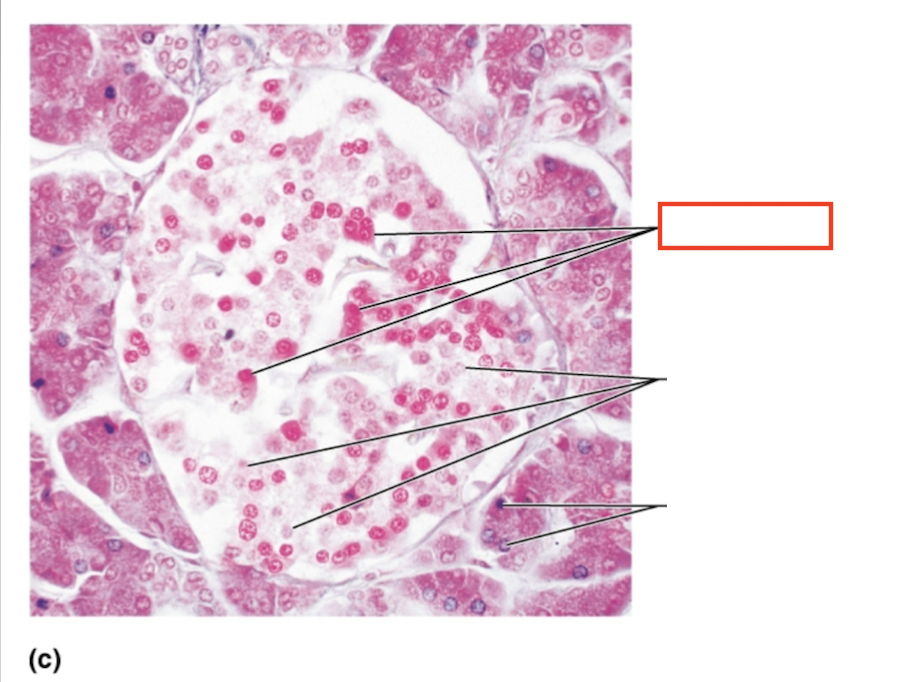

What structure is highlighted?

alpha cells (glucagon producing)

What structure is highlighted?

beta cells (insulin producing)

What structure is highlighted?

pancreatic acinar cells (exocrine)

What tissue is shown?

pancreatic islet

What hormones are released by the pancreas?

insulin, glucagon

What are the target organs and effects of insulin

most cells of the body, accelerates the transport of glucose into body cells; promotes glycogen, fat, and protein synthesis

What are the target organs and effects of glucagon?

primarily the liver and adipose; accelerates the breakdown of glycogen to glucose, stimulates the conversion of lactic acid into glucose, releases glucose into the blood from the liver

What stimulates glucagon production?

decreased blood glucose levels, sympathetic nervous system stimulation

What stimulates insulin production?

increased blood glucose levels, parasympathetic nervous system stimulation